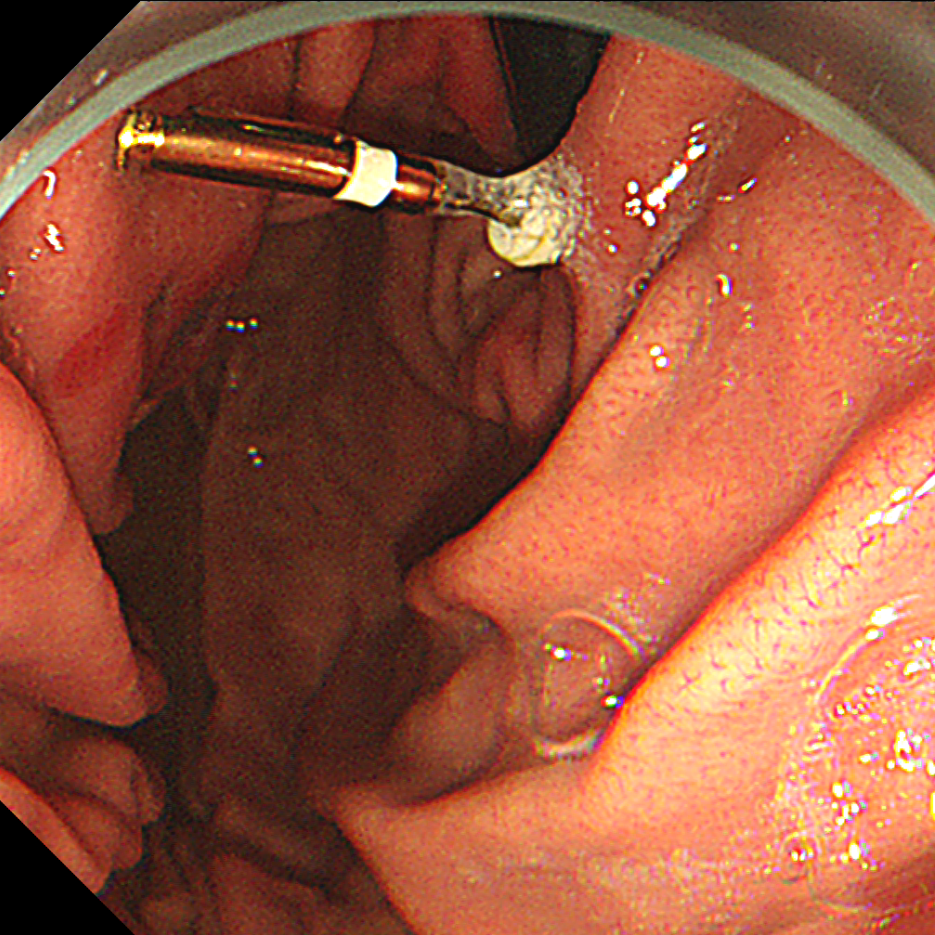

一位男士在小诊所治疗时,不慎将一段长约 4 cm 的金属口腔器械滑入胃中,当时几乎未感任何不适。然而胃镜下的一幕却令医生警惕:那截金属如一枚「暗箭」,斜斜扎在胃体上部黏膜中,从误吞到检查,仅仅一天,胃内已出现明显的糜烂溃疡表现。

医生表示,这类「沉默的异物」极具隐匿风险,若不及时取出,可能导致胃穿孔或大出血等严重并发症。